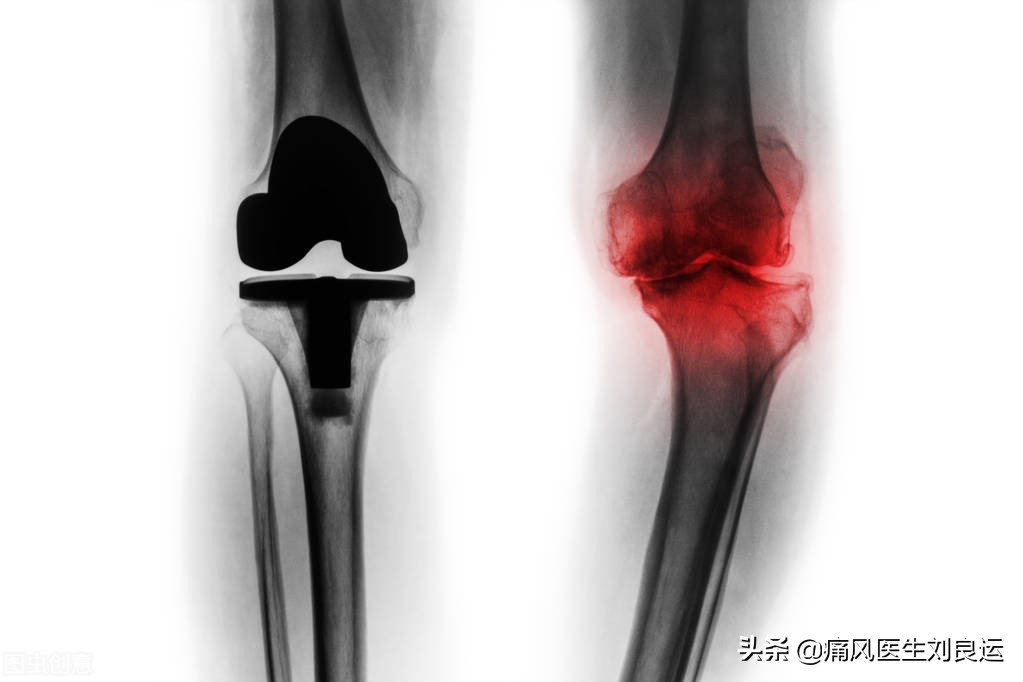

膝关节严重退行性关节炎病变